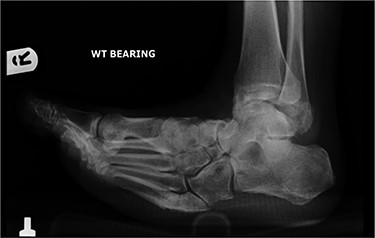

In May 2015, he had a complex midfoot reconstruction, but his foot continued to drift into varus. This was complicated by an infected ulcer on the lateral aspect of midfoot (Fig. 3). Wound infection progressed to osteomyelitis, and in May 2018, he had a hindfoot reconstruction with fusion of tibiotalar and subtalar joints using a Cerament-V-coated hindfoot nail (Figs 4 and 5).

Lateral radiograph of right ankle demonstrating tibiotalocalcaneal fusion using a hindfoot nail and screws.